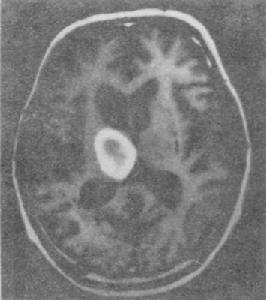

新生兒出血症--CT凝血酶原時間和部分凝血活酶時間延長,血小板正常。測定活性Ⅱ因子與Ⅱ因子總量比值兩者比值小於1時提示維生素K缺乏。測定無活性凝血酶原用免疫學方法直硬定無活性凝血酶原,陽性提示維生素K缺乏。出血者可給予維生素K1,1-2mg靜脈滴注,出血可迅速停止,通常2小時內凝血因子水平和功能上升,24小時完全糾正。嚴重者可輸新鮮冰凍血漿10-20ml/kg,以提高血漿中有活性的凝血因子水平。產婦分娩前l周,給維生素K肌注或口服,有預防作用。肌注維生素K一日2-4毫克,連續3-4日。出血量多,需緊急輸血。嚴重胃腸道出血,應暫停餵乳。